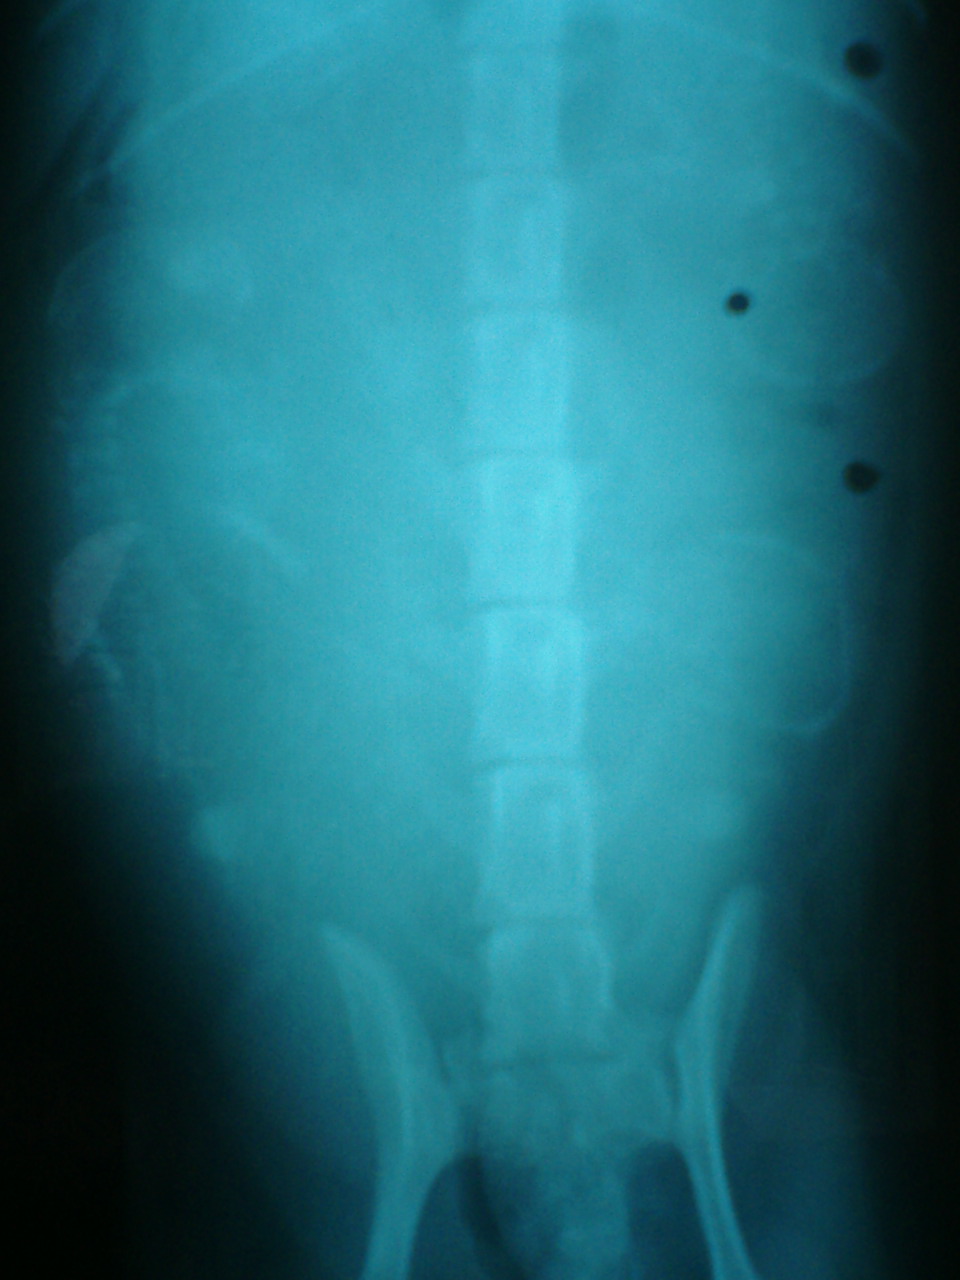

桃のレントゲン写真

解りづらいのですが、右側に2つ、

左側に1つ頭が写っています。